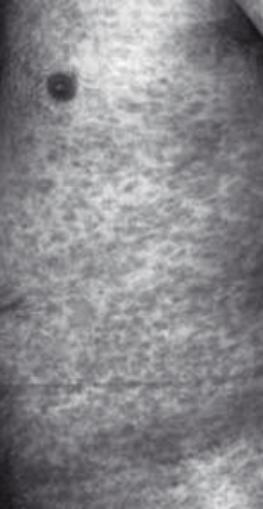

Sifilide I stadio (pene)

Sifilide II stadio (torace)

Evoluzione:

Sifilide III stadio (piedi)